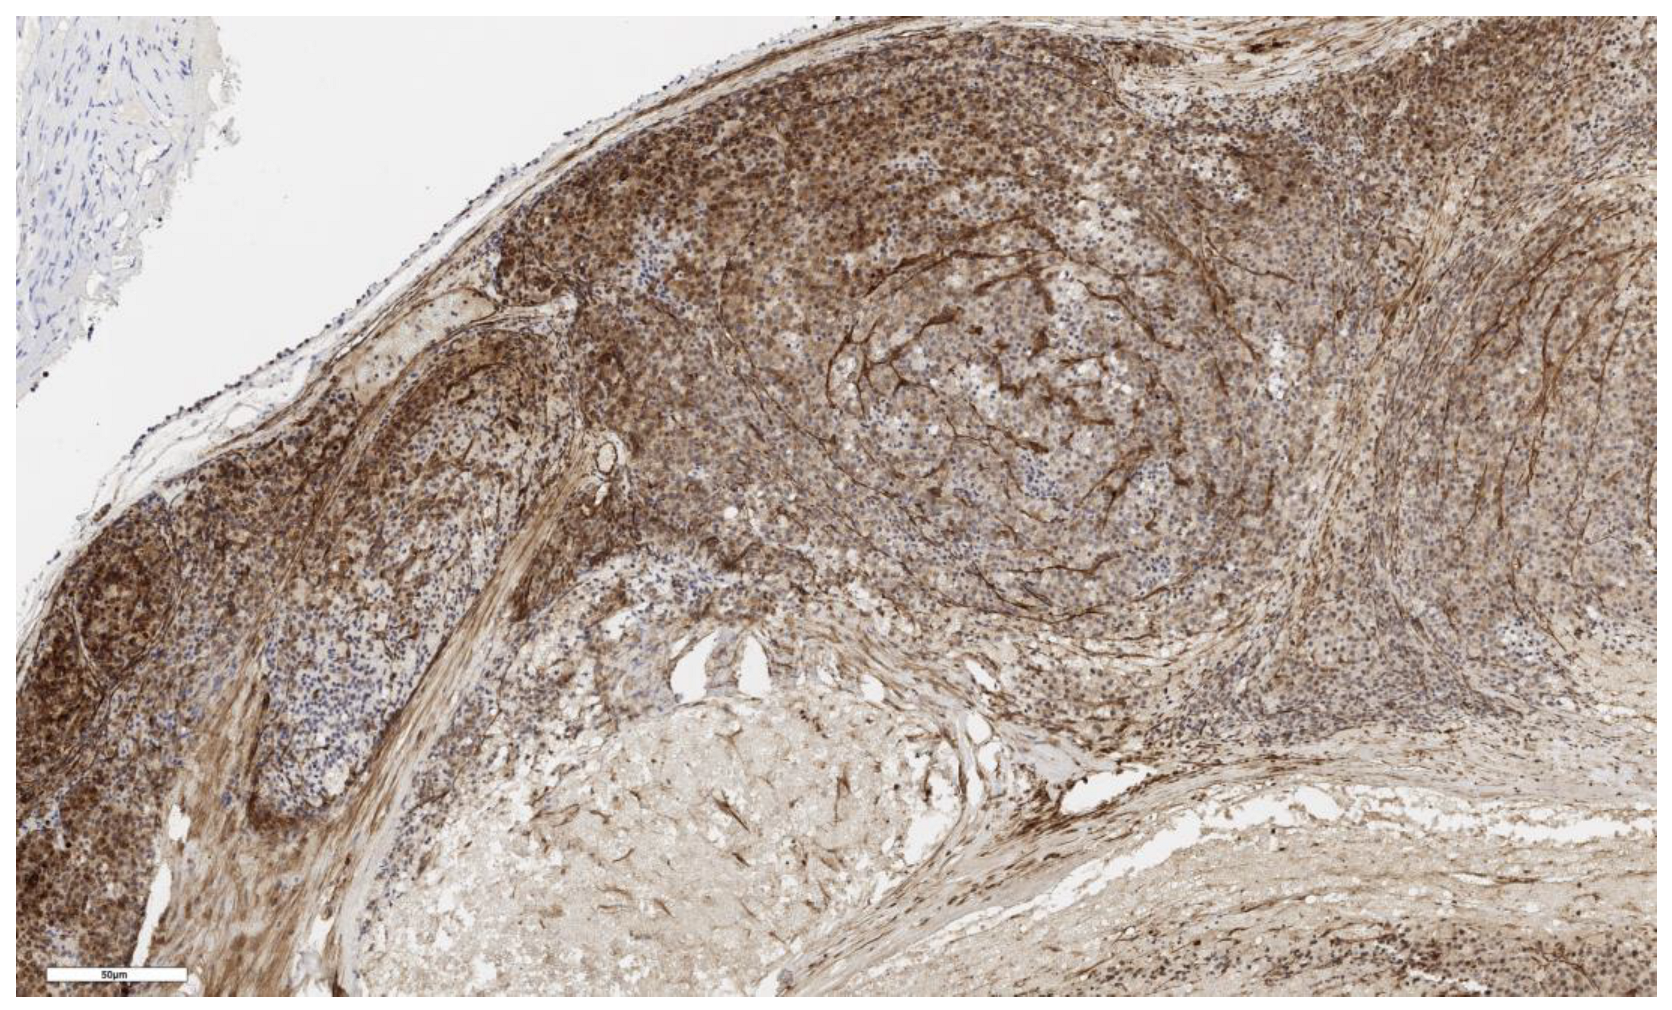

3.1. Analysis of CD90 Marker Expression

3.2. Analysis of LGR5 Marker Expression

3.4. Analysis of Stem Marker Expression in Normal Adrenal Tissue